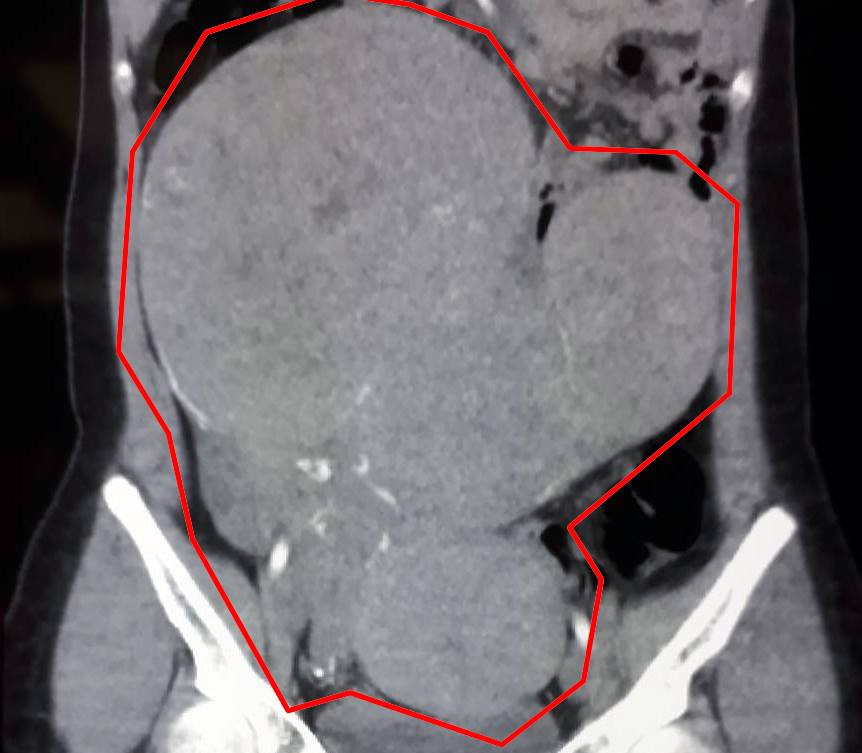

Tại đây, các bác sĩ đã phát hiện bệnh nhân có khối bướu kích thước khá lớn ở thành tử cung chiếm toàn bộ ổ bụng.

| khối bướu gần 4 kg trong bụng cô gái. Ảnh: BSCC. |

Sau một tiếng các bác sĩ đã bóc tách thành công khối bướu nặng gần 4 kg ra khỏi người bệnh nhân. Hiện sức khỏe cô gái đã ổn định.